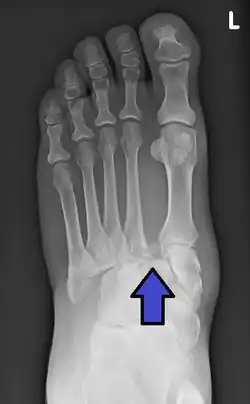

| An X-ray of a Lisfranc injury | |

In a high energy injury to the midfoot, such as a fall from a height or a motor vehicle accident, the diagnosis of a Lisfranc injury should, in theory at least, pose less of a challenge. There will be deformity of the midfoot and X-ray abnormalities should be obvious. Further, the nature of the injury will create heightened clinical suspicion and there may even be disruption of the overlying skin and compromise of the blood supply. Typical X-ray findings would include a gap between the base of the first and second toes.[8] The diagnosis becomes more challenging in the case of low energy incidents, such as might occur with a twisting injury on the racquetball court, or when an American Football lineman is forced back upon a foot that is already in a fully plantar flexed position. Then, there may only be complaint of inability to bear weight and some mild swelling of the forefoot or midfoot. Bruising of the arch has been described as diagnostic in these circumstances but may well be absent.[9] Typically, conventional radiography of the foot is utilized with standard non-weight bearing views, supplemented by weight-bearing views which may demonstrate widening of the interval between the first and second toes, if the initial views fail to show abnormality. Unfortunately, radiographs in such circumstances have a sensitivity of 50% when non-weight bearing and 85% when weight-bearing, meaning that they will appear normal in 15% of cases where a Lisfranc injury actually exists.[10] In the case of apparently normal x-rays, if clinical suspicion remains, advanced imaging such as magnetic resonance imaging (MRI) or computed tomography (CT scan) is a logical next step.[11]